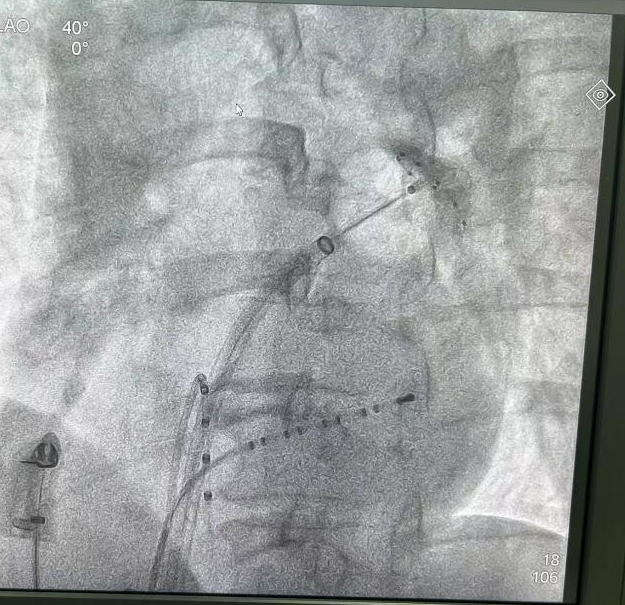

心血管内科副主任陈弹带领电生理团队对范阿姨的左心房三维重建图像进行仔细分析,并在多次病例讨论后认为范阿姨更适合采用安全性更高、更高效的“冷冻球囊消融”手段治疗。在医护人员的通力合作下,陈弹副主任带领团队为患者实施消融手术。术中,冷冻球囊完美贴合四个肺静脉开口并成功隔离肺静脉电位,手术取得圆满成功。

陈主任介绍道,阵发性房颤发生的主要机制在于肺静脉等部位的肌袖心房肌的异常电活动,所以隔离肺静脉是房颤消融治疗的基石。目前,治疗手术手段根据消融能源不同分为“射频消融术”和“冷冻球囊导管消融术”两类。相比于射频消融,冷冻球囊消融对于阵发性房颤的病患具有手术时间短,并发症发生率低的优势,并且治疗效果不劣于射频消融,是目前首选治疗方法之一。